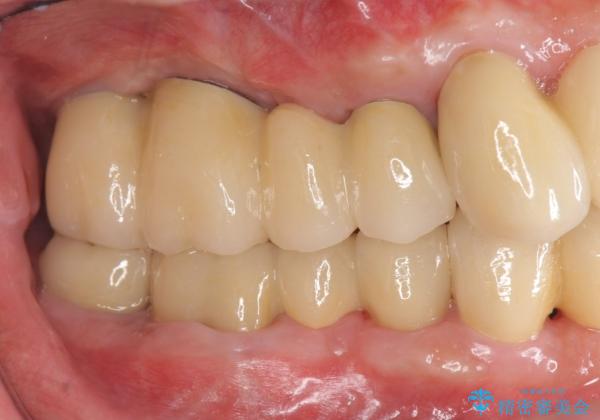

インプラントを用いた咬合機能回復治療

- 「歯がぐらぐらして噛めない、歯を抜いて欲しい、またしっかりと噛めるようになりたい。」、と歯周病治療を希望され来院されました。

重度に吸収してしまった歯槽骨をしっかりと造成を行ったのちにインプラント治療を行ったので、安定した歯周環境にすることができました。